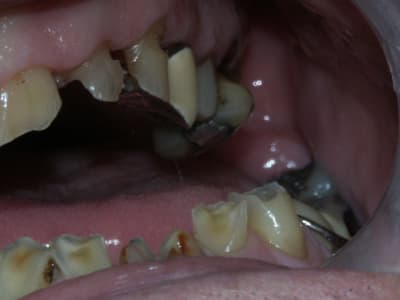

la suite...

J'ai fait une RA de 22, elle est très courte et cariée assez sous gingivale. Pas sûr du tout de la conserver.

Suis pas très chaud pour garder la 12 (LPA sous richmond)

Il y a une péche sous 26. Faut qu'on soit sûr de la garder avant de se lancer dans un bridge.

J'ai pensé aussi comme toi au bridge 32-42 mais la forme de la racine de 32 n'est pas idéale.

Il conviendrait d'augmenter la DV partout mais on risque de se retrouver avec les difficultés suivantes:

- en postérieur, l'augmentation de DV sera importante et on risque de vite se retrouver avec des couronnes avec un rapport couronne / racine défavorable.

- en antérieur, le gain de DV obtenu sera plus faible du fait de l'égression physiologique des dents. Le dilemne est de savoir si cela permettra d'avoir assez de place pour faire des couronnes.

Pour gagner un peu de hauteur sur les dents antérieures pour les futures CCM, je pensais faire des gingivectomies. Les bruxos ont souvent un parodonte en béton avec de la GA à revendre, favorable à cette technique. Cela permettrait de limiter l'augmentation de DV. Le seul truc qui coince c'est que le patient n'a pas des racines très longues.